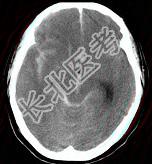

- 单项选择题成年男性,外伤后一小时出现头痛, 呕吐,查体: 颈项强直。CT检查如图,最可能的诊断是 ( )

A、硬膜外血肿

B、脑出血

C、正常脑CT

D、硬膜下血肿

E、蛛网膜下隙出血